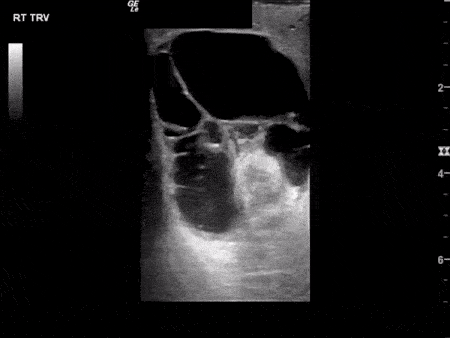

Renal/GU - Epididymitis with Complex Hydrocele

This image demonstrates fluid filling the scrotal sac with multiple thin septations consistent with a complex hydrocele. In the setting of epididymitis, a pyocele should be considered. Image courtesy of Aventura Ultrasound See Original Post Via their Twiiter: @AventuraEUS